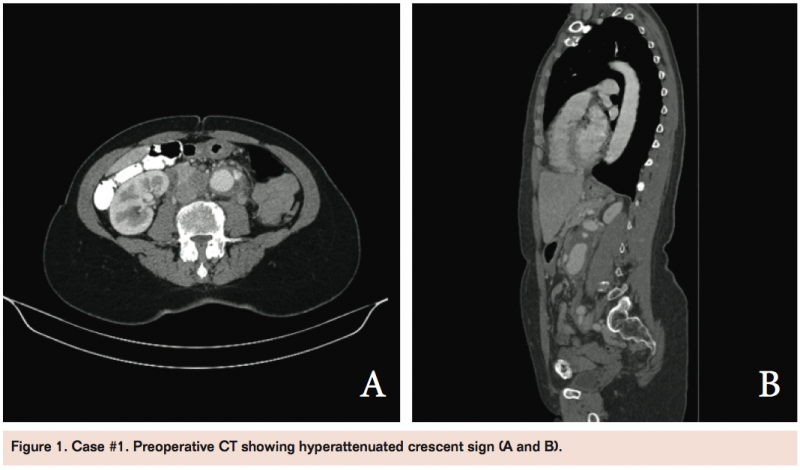

Initial evaluation included an ultrasound and CT scan, both revealing a 5.7 cm infrarenal AAA with positive crescent sign noted on CT (Figure 1). The patient was transferred to a local tertiary care facility where she was evaluated by vascular surgery and critical care service. The patient was admitted to the intensive care unit (ICU) for blood pressure control (target systolic 90-120 mm Hg) with labetalol drip, as well as intravenous maintenance fluids, analgesics, and antiemetics. The patient was monitored with serial exams and prepared for endovascular repair the following day.

After an uneventful preoperative night, the patient was taken to the operating room (OR) the morning of hospital day 2 for a semi-urgent repair. The size and anatomy of the aneurysm were amenable to EVAR. After obtaining bilateral femoral access, a marker pigtail catheter was placed into the suprarenal abdominal aorta for aortography. Extravasation of contrast from the mid left lateral portion of aneurysm sac again demonstrated the same crescent sign noted on CT (Figure 2).